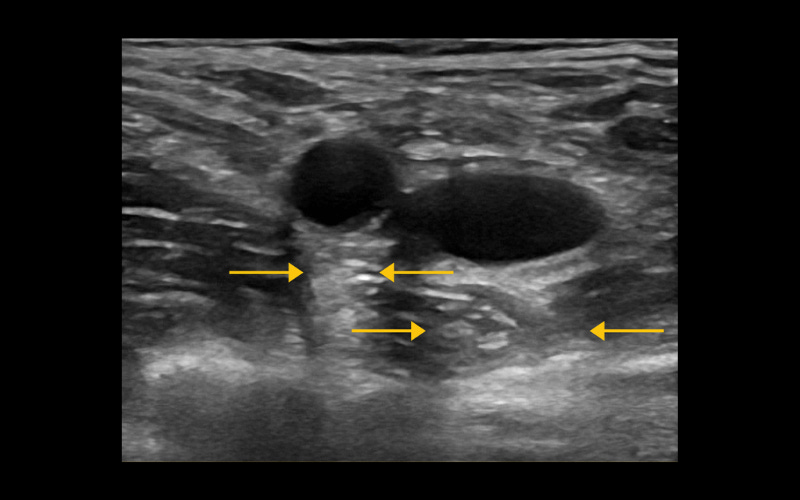

Sombra acústica por refracción

"Es la sombra que se produce debido a la pérdida del haz de ultrasonido cuando este entre en contacto con estructuras redondas u ovaladas."

Refuerzo acústico posterior

"Se observa como una sombra con mayor aumento de la ecogenicidad profundo a los líquidos."

Como puedes observar, en una misma imagen ecográfica pueden existir diferentes tipos de Artefacto (Refuerzo acústico posterior y Sombra acústica por refracción)